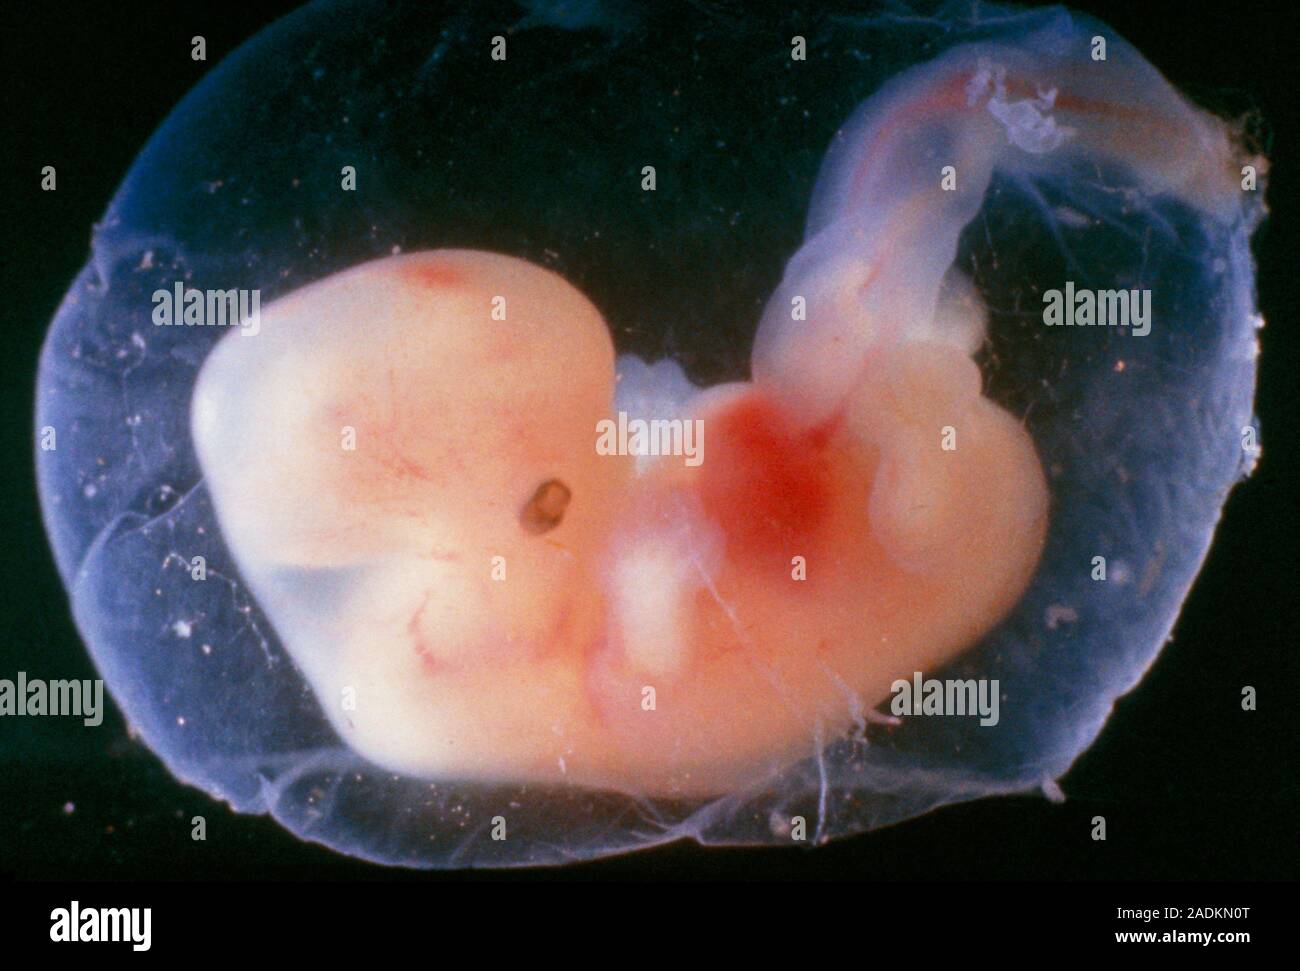

Эмбриональный период: Развитие эмбриона от зачатия до рождения